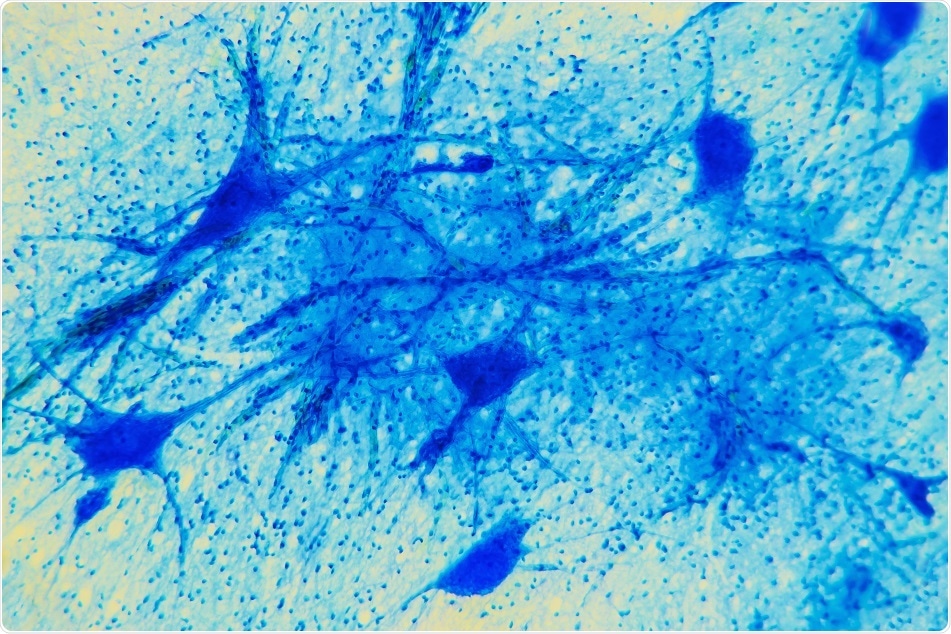

Credit: Digital Photo / Shutterstock.com

A thread-like projection known as a process is present in the front of the cell body or soma of the baby neurons; directed by numerous signals, it stretches forward via the tunnel. Simultaneously, the soma that is lagging behind is pushed forward from the rear through the activation of minute molecular motors.

A number of cells move together, one on top of the other, like a group of small worms creeping forward by altering their body shape.